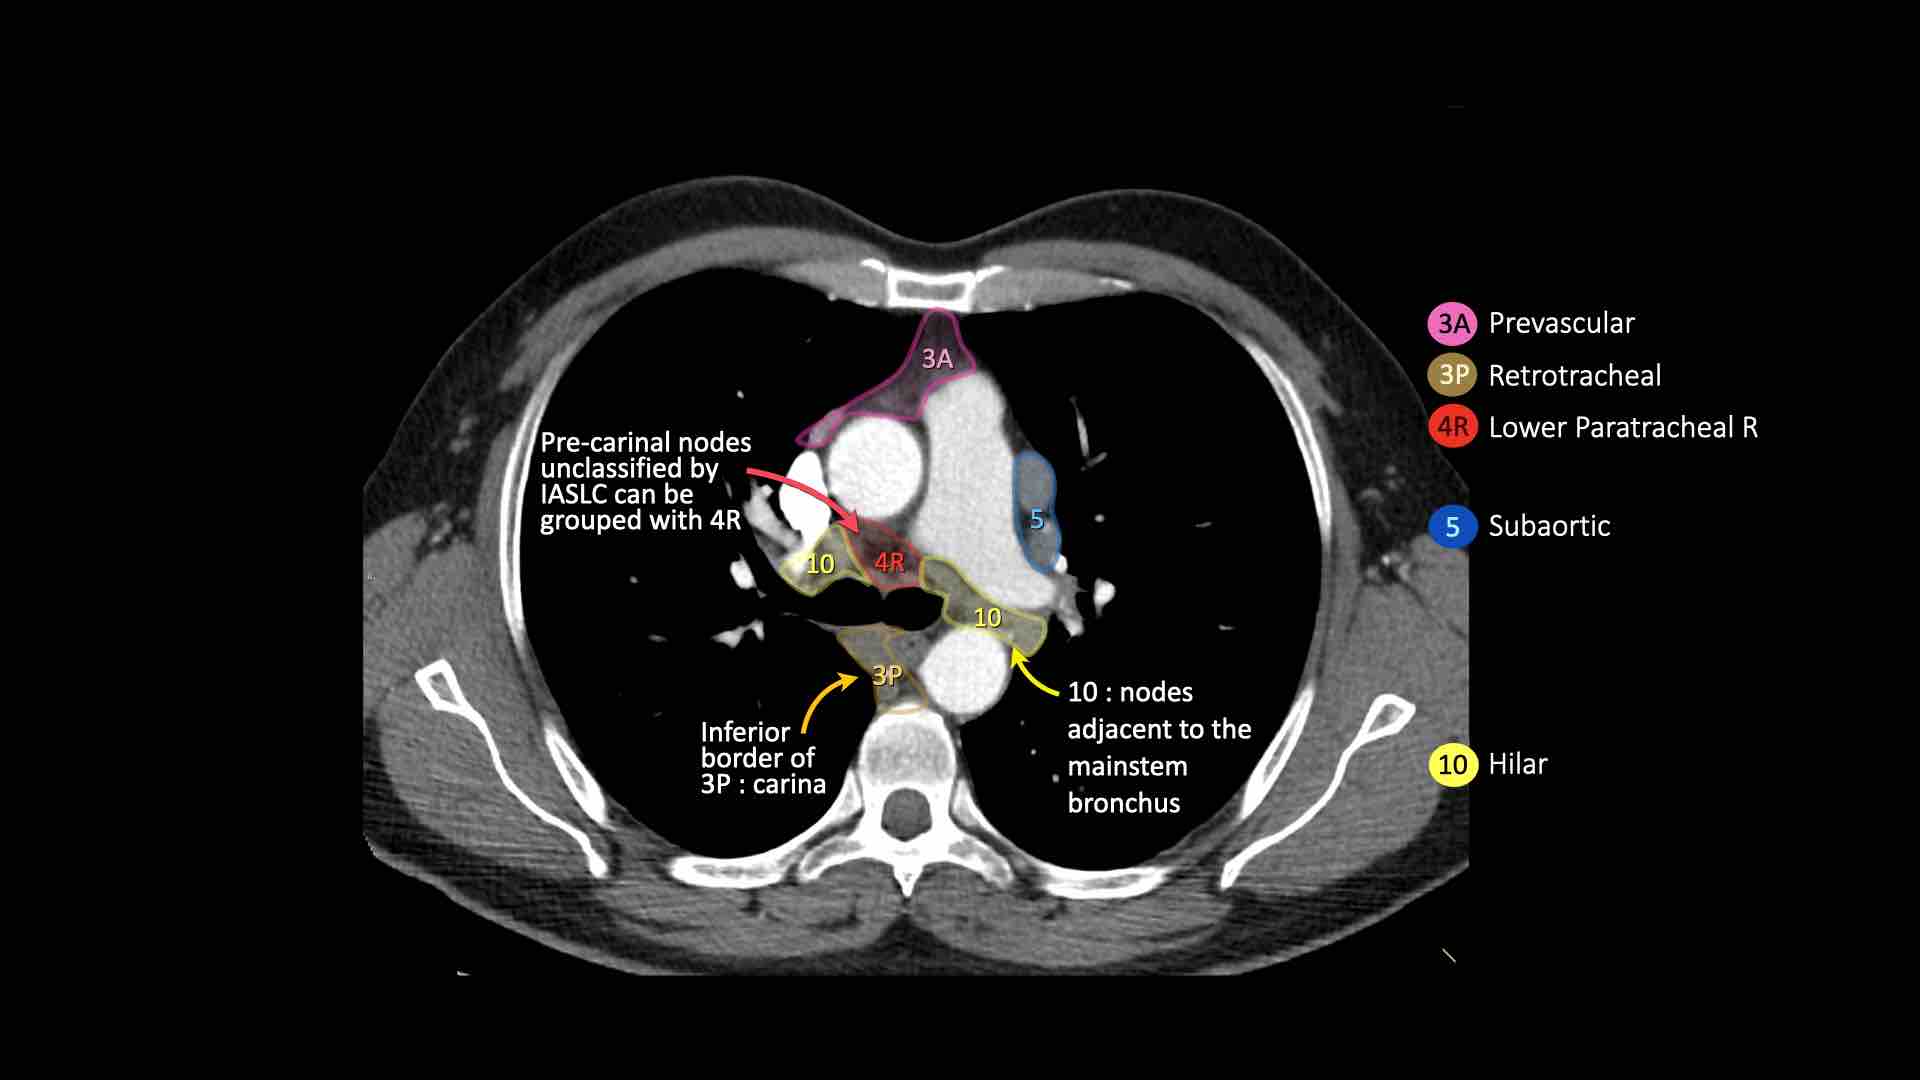

3A.Trước mạch máu

Các hạch này không tiếp giáp với khí quản như các hạch ở nhóm 2, mà nằm ở phía trước các mạch máu.

3P.Trước cột sống

Các hạch không tiếp giáp với khí quản như các hạch ở nhóm 2, mà nằm sau thực quản, tức là ở vị trí trước cột sống.

4R.Cạnh khí quản dưới

Từ điểm giao nhau giữa bờ dưới tĩnh mạch vô danh (tĩnh mạch tay đầu trái) với khí quản đến bờ dưới tĩnh mạch đơn.

Hạch nhóm 4R trải dài từ bờ bên phải đến bờ bên trái của khí quản.

10. Hạch rốn phổi

Bao gồm các hạch tiếp giáp với phế quản gốc và các mạch máu rốn phổi.

Hạch rốn phổi là các hạch thùy gần, nằm ở phía xa so với nếp gấp màng phổi trung thất và các hạch kề phế quản trung gian bên phải.